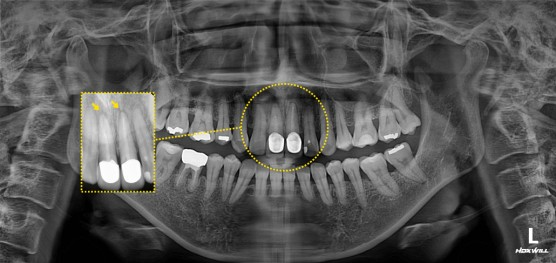

재신경치료 후 보철 치료

#11,21 뿌리 끝에 염증있어서 re-endo후 post cr설명 드리고 진행함.

[부작용 안내]

신경치료 후 감염, 염증, 통증 등의 부작용이 발생할 수 있으며, 크라운 보철치료 후 부작용은 보철이 잘못 만들어졌을 때 하악 통증, 편두통 등이 있을 수 있습니다. 또 보철 마모 및 탈락이 있을 수 있습니다.

※ 상기 사진은 본원 권대근 대표원장이 치료한 환자분의 동의를 받은 이미지 사진으로 실제와 차이가 있을 수 있습니다.